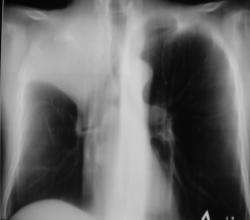

На иллюстрациях 1, 2. Представлены флюорограммы, произведенные в «настоящее время». На флюорограмме, произведенной в прямой стандартной проекции, визуализируется снижение прозрачности легочной ткани верхней доли правого лёгкого однородной структуры, без четких контуров. Правый корень несколько подтянут кверху, что навело на мысль об ателектазе. На боковой флюорограмме дифференцируется снижение прозрачности верхней доли средней интенсивности, однородной структуры с четкими «вогнутыми контурами», имеет место уплотнение структур корня с «кажущейся тяжистостью» кпереди, в средней доле. В грудном отделе позвоночника явления межпозвонкового остеохондроза.